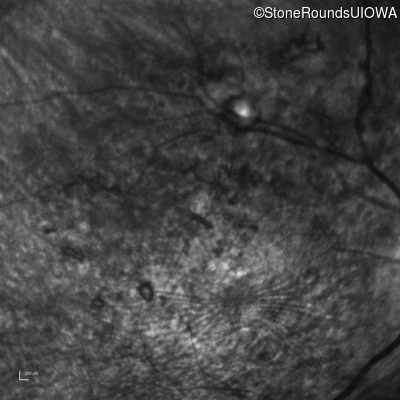

Infrared Fundus Photograph - Right - 20/400 sc

Exemplar